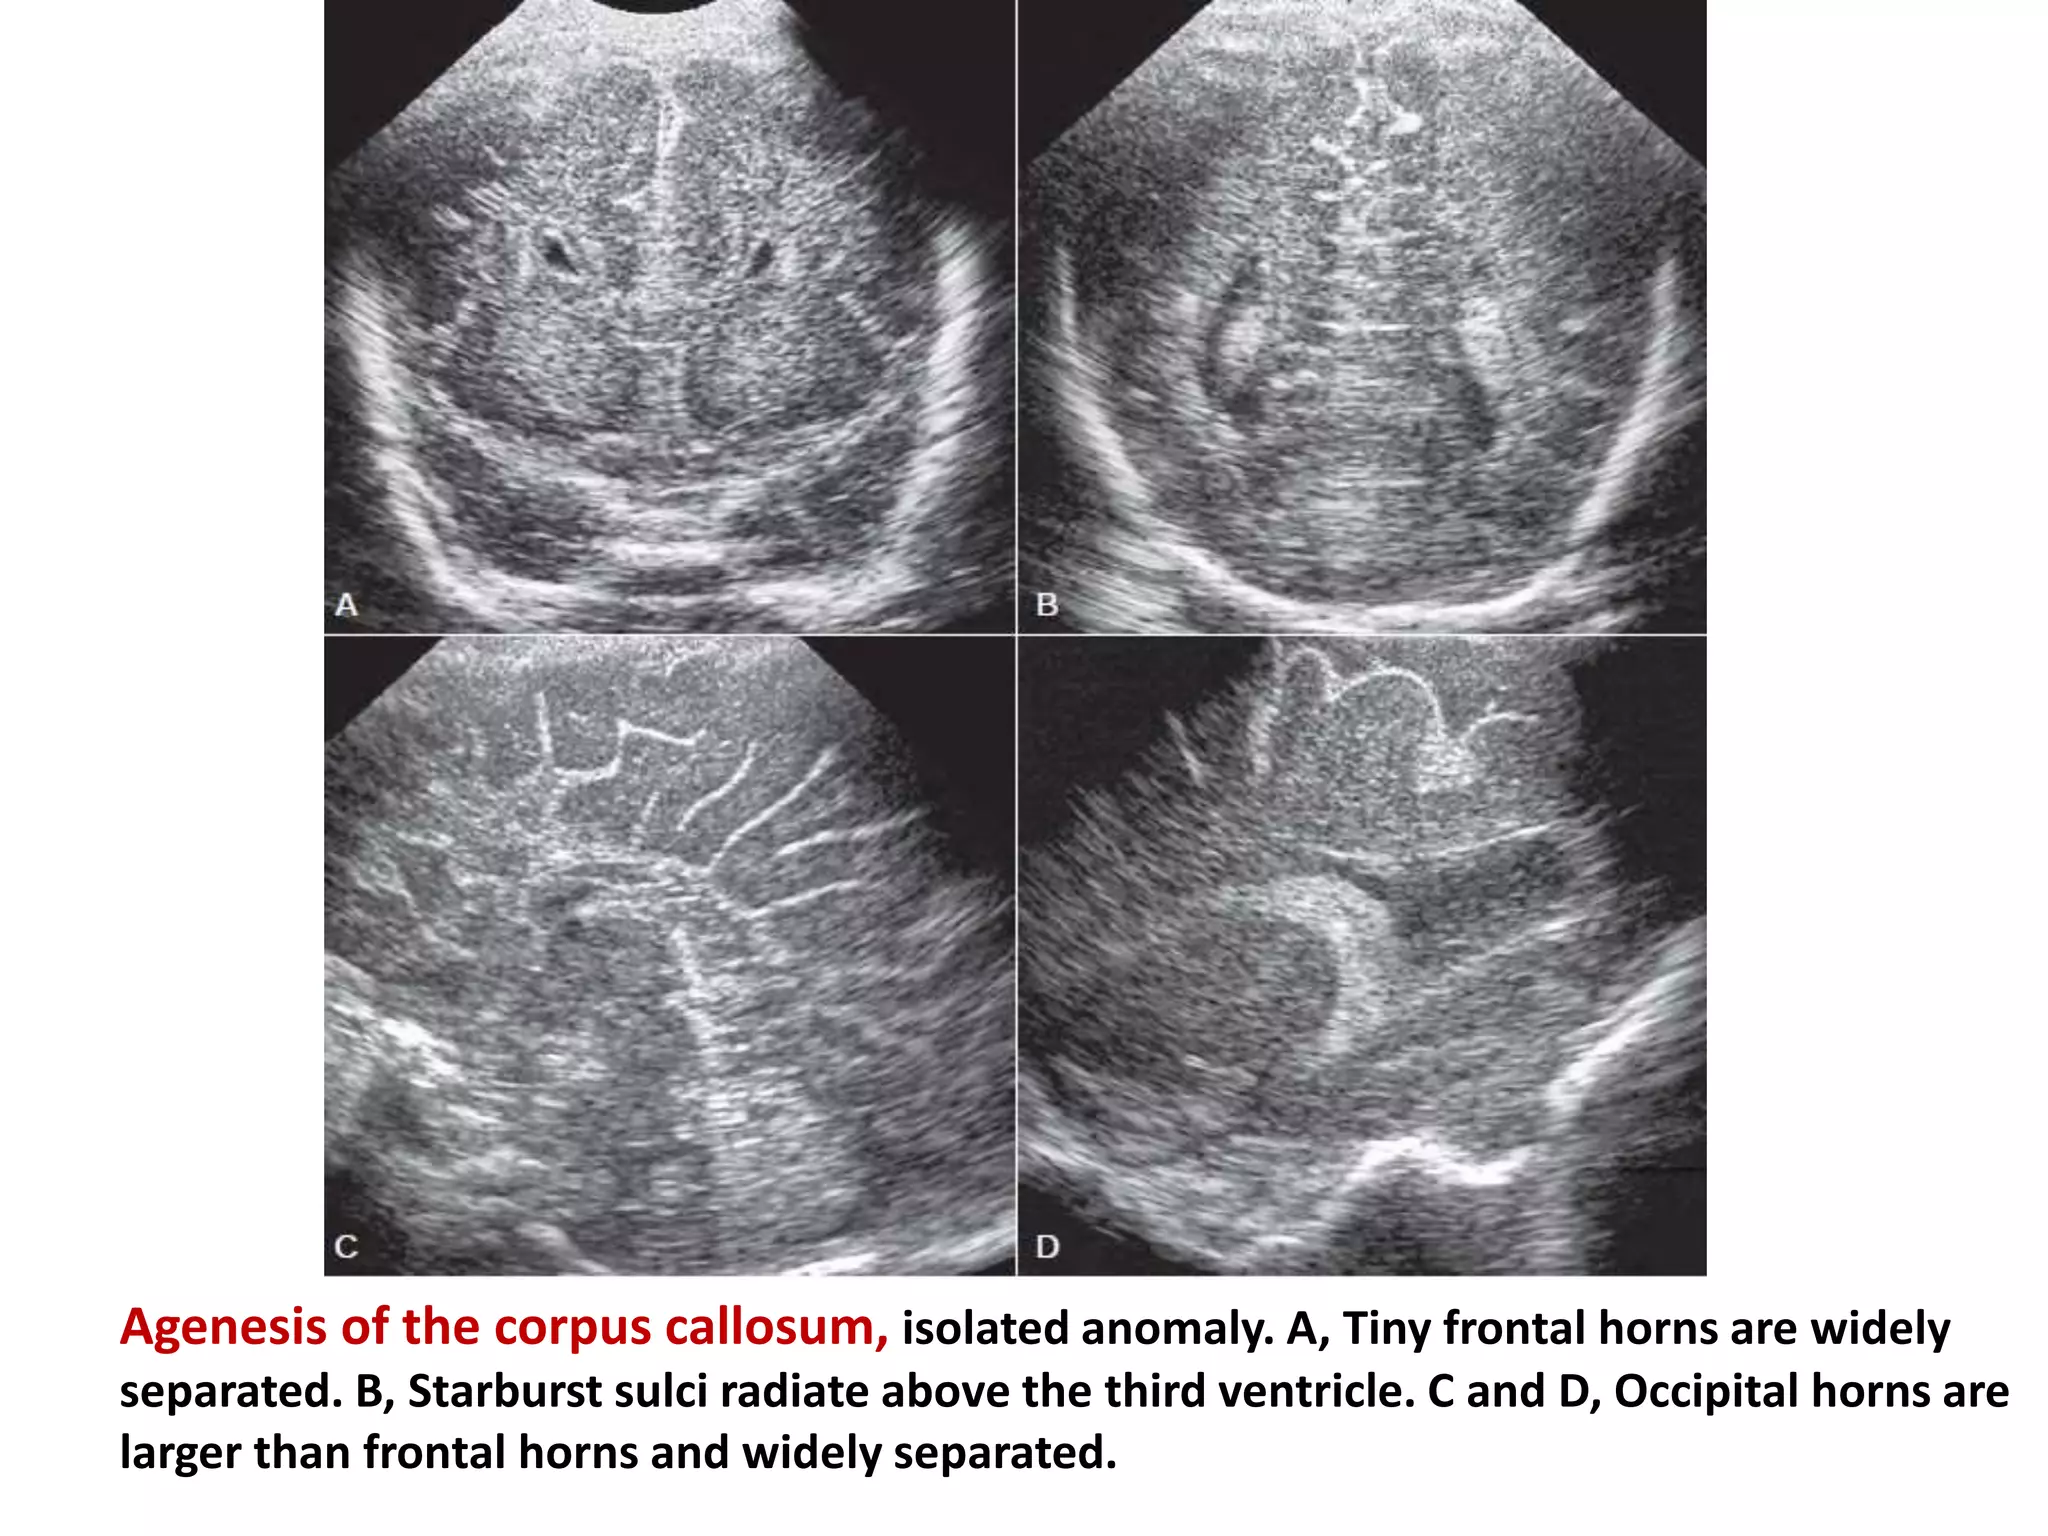

Agenesis of Corpus Callosum

•depending on the timing of the intrauterine insult,

development of corpus callosum may be partially or

completely arrested . If partial, the genu is usually

present, and the dorsal splenium or the anterior

rostrum is absent.

•associated anomalies include

Chiari II and Dandy-Walker malformations,

holoprosencephaly, encephaloceles, lipomas,

arachnoid cysts, migrational abnormalities, and

Aicardi syndrome

Agenesis of the corpus callosum, isolated anomaly. A, Tiny frontal horns are widely

separated. B, Starburst sulci radiate above the third ventricle. C and D, Occipital horns are

larger than frontal horns and widely separated.

Agenesis of CorpusCallosum •depending on the timing of the intrauterine insult, development of corpus callosum may be partially or completely arrested . If partial, the genu is usually present, and the dorsal splenium or the anterior rostrum is absent. •associated anomalies include Chiari II and Dandy-Walker malformations, holoprosencephaly, encephaloceles, lipomas, arachnoid cysts, migrational abnormalities, and Aicardi syndrome

Agenesis of thecorpus callosum, isolated anomaly. A, Tiny frontal horns are widely separated. B, Starburst sulci radiate above the third ventricle. C and D, Occipital horns are larger than frontal horns and widely separated.